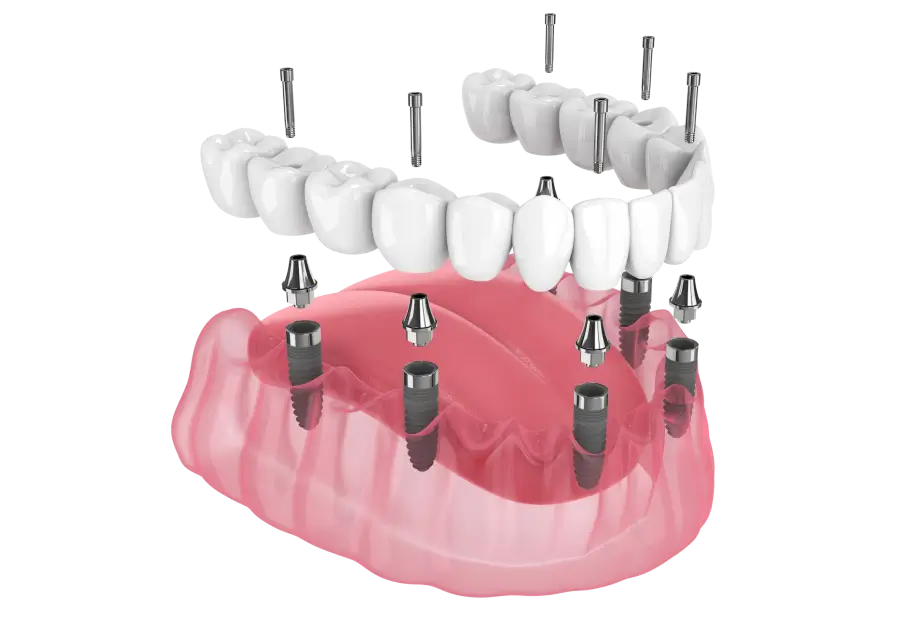

Імплантація All-on-4

Одним із методів відновлення повністю беззубої щелепи є імплантація All-on-4 — фіксація протеза на чотирьох дентальних імплантах.

- опора протеза на 4 імпланти

- імпланти встановлюються під спеціальним кутом для кращої стабільності

- часто дозволяє уникнути кісткової пластики

Метод All-on-4 дозволяє надійно зафіксувати протез і відновити функцію жування навіть при значній втраті зубів.

Імплантація All-on-6

Метод All-on-6 застосовується для відновлення повністю беззубої щелепи з опорою на шість дентальних імплантів.

- протез фіксується на 6 імплантах

- підвищена стабільність конструкції

- показана для пацієнтів більш молодшого віку

Такий метод дозволяє створити міцну та довговічну опору для незнімного протеза і відновити повноцінну функцію зубного ряду.